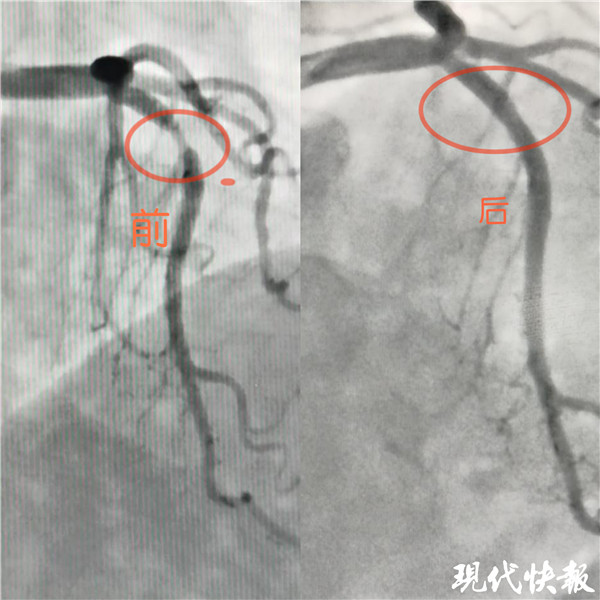

記者了解到,入院后完善冠狀動脈造影檢查示,張女士LM正常,LAD近段血管90%狹窄, LCX及RCA未見狹窄?;窗彩幸辉盒膬?nèi)科介入治療團(tuán)隊嚴(yán)格把握適應(yīng)癥,和患者及家屬溝通后,于LAD病變處植入一枚藥物可吸收支架,術(shù)后血管內(nèi)超聲檢查提示支架貼壁良好。